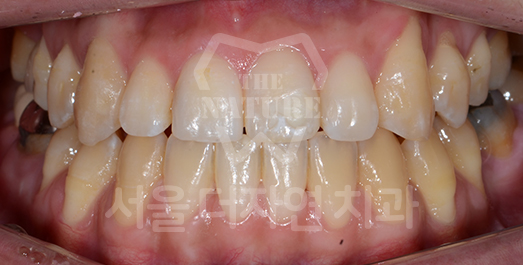

덧니 교정 Solution

덧니는 치아가 올라올 공간이 부족하여

제자리에 올라오지 못하는 상태를 말합니다.

덧니를 오랫동안 방치할 경우 칫솔질이 제대로 되지 않아

치아 사이에 음식물이 잘 끼고, 충치가 생길 위험이 큽니다.

또한 치주 질환의 원인이 되므로

교정치료를 통해 개선하는 것이 바람직합니다.

BEFORE: 2020.06.11

AFTER: 2023.02.02